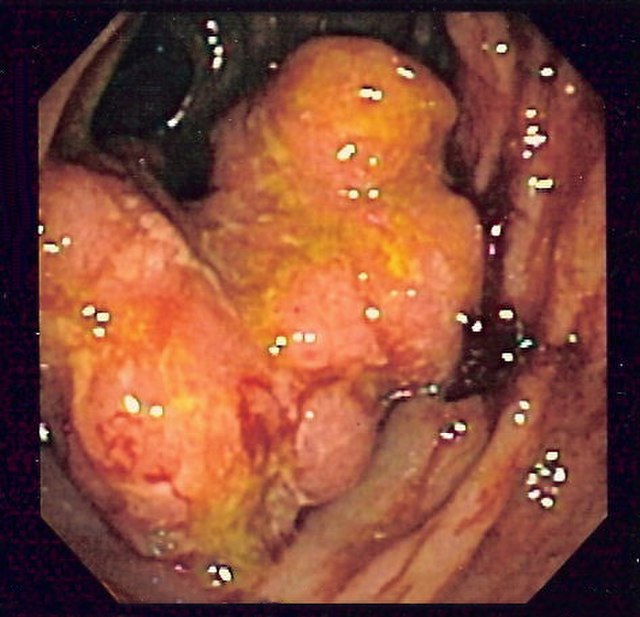

Sometimes the tumours grow deep inside the body. If there is plenty of room for them to grow before they cause symptoms, they can easily become very big and have formed many metastases before the person affected becomes aware of the problem. Lung cancers, stomach cancers and bowel cancers are rather like this.

Intra Camera